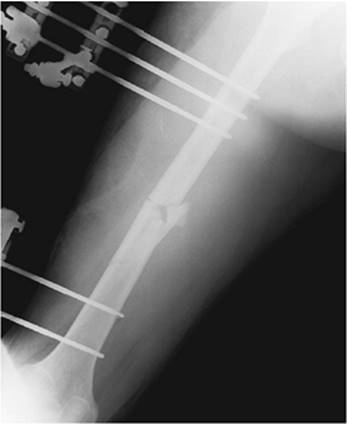

Approximately 70 years ago, the technique of closed IM nailing was developed. This technique involves making a small incision proximally or distally in the extremity. The fracture fragments are then reduced manually under fluoroscopic visualization. The medullary canal is accessed and a guidewire is placed across the fracture. A nail is then driven up the medullary canal over the guidewire to sterilize the bone. If desired, the canal can be reamed before the nail is placed. The nail can be locked in place by placing several screws in the very proximal or distal portion of the nail through a secondary small incision. These screws are placed under fluoroscopic control (Fig. 85.4).

Figure 85.4. The fracture was treated with early intramedullary nail fixation. With early fixation of femoral fractures in multiply injured patients, many pulmonary problems can be avoided. Stable fixation of even complex, comminuted injuries can allow early weight bearing and facilitate functional rehabilitation despite polytrauma.